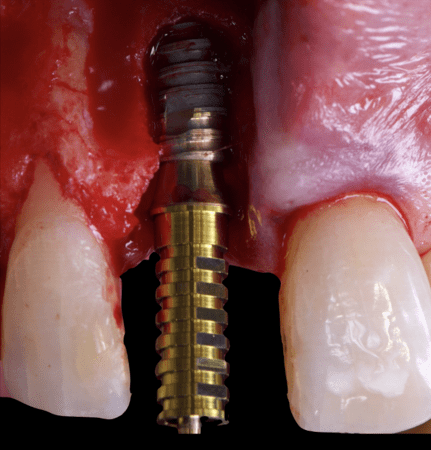

The surgical protocol began with the atraumatic extraction of tooth 1.1 to preserve as much of the alveolar socket as possible. Immediately following extraction, an N1 implant was placed into the socket using a guided surgical approach to ensure ideal three-dimensional positioning. The “one abutment one time” technique was applied to minimize soft tissue manipulation during the healing phase, which is particularly important in esthetic areas.

Given the significant buccal defect, guided bone regeneration (GBR) was performed simultaneously. A mixture of autologous bone and creos™ xenogain™ was applied to the defect and covered with a resorbable creos™ membrane to restore ridge width and support the buccal contour. In addition, a connective tissue graft was harvested and placed in the vestibular region to increase the thickness of keratinized mucosa. This combined approach addressed both hard and soft tissue deficiencies, providing the biological foundation for a stable and esthetic outcome.

On the same day as the surgery, an immediate-load provisional crown was delivered. This restoration was fabricated in acrylic resin and screw-retained on the implant, following the “one abutment one time” principle. The provisional crown was carefully adjusted to avoid occlusal loading while supporting the peri-implant soft tissue architecture during the healing phase.